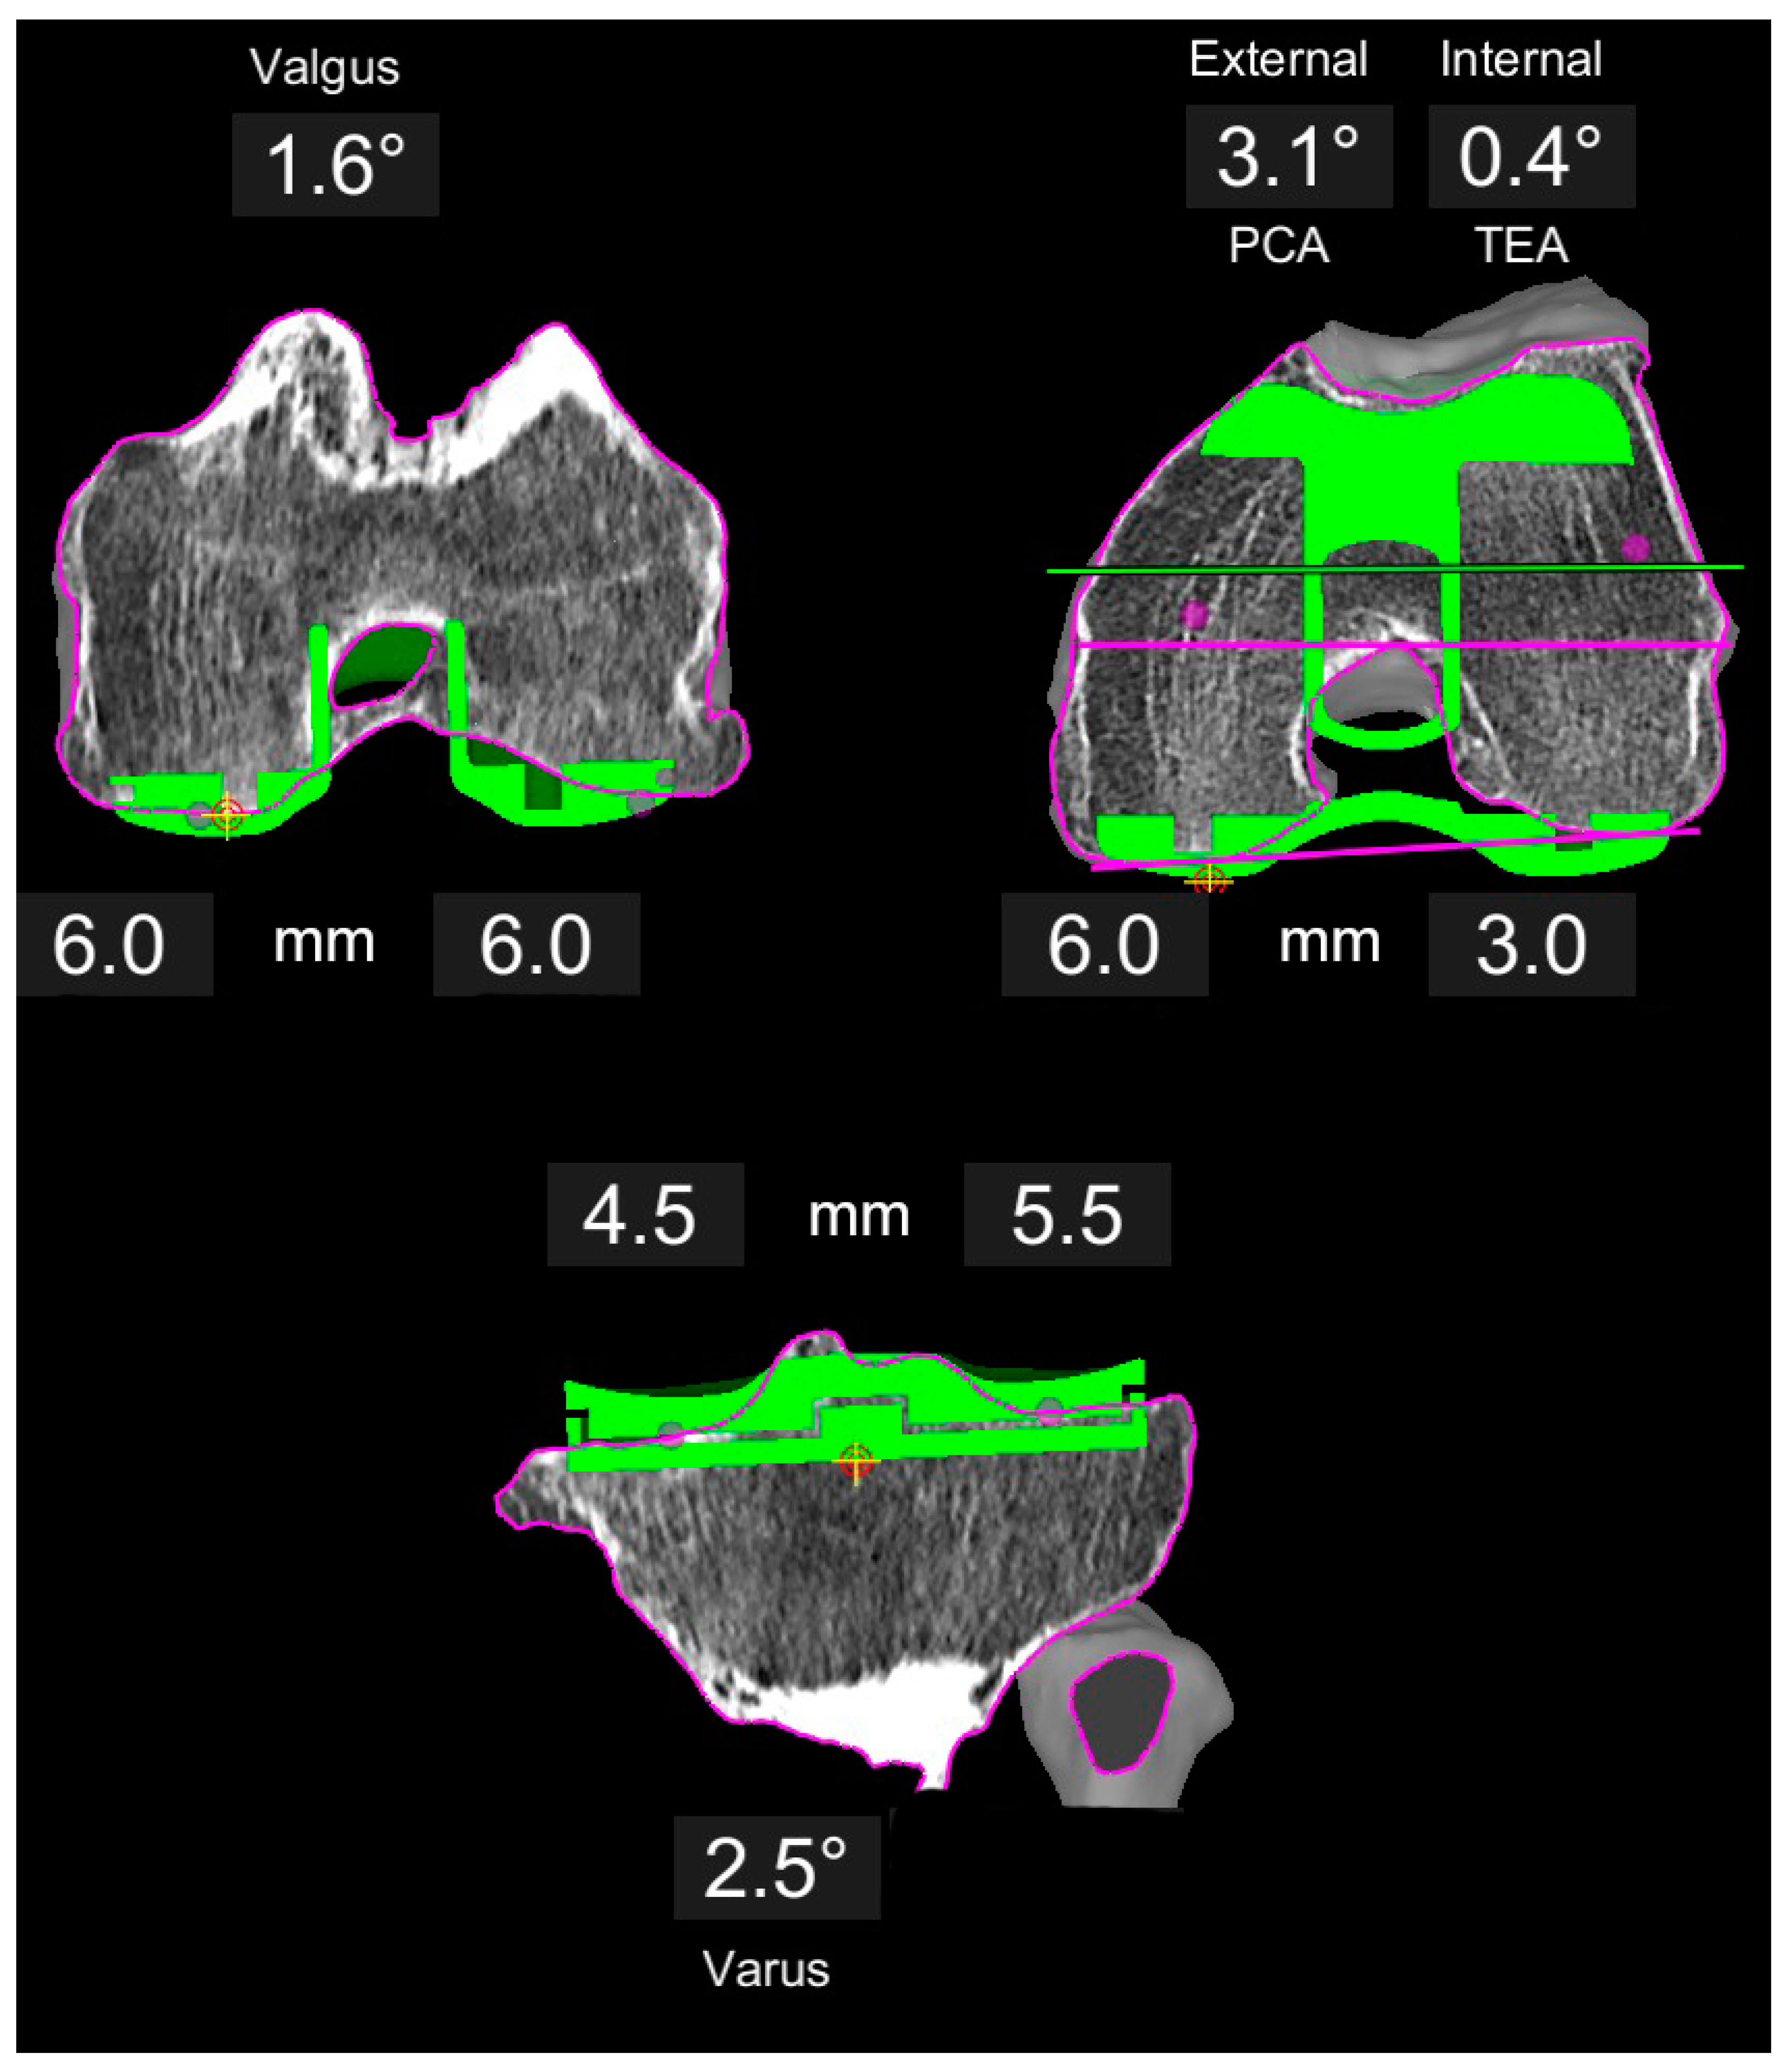

Figure 2.

Example of a varus knee planned with restricted KA. The distal femoral resection is symmetric at 6 mm, whereas the posterior resection is adjusted to co-align the trochlea groove close to the native trochlea axis. This results in a 3.1° external rotation with respect to the PCA. Tibia follows the same principle as for KA (Figure 1).